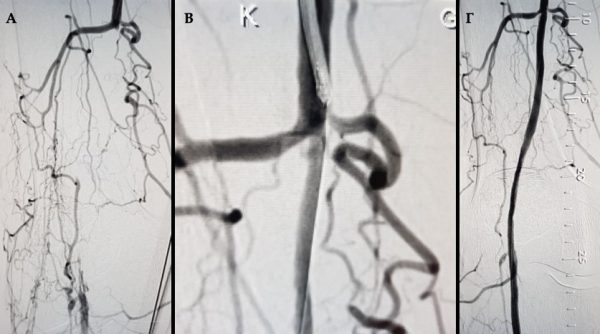

Εικόνα 2. Δημιουργία φίστουλας μεταξύ αρτηρίας και φλεβών του κάτω άκρου: Τα αγγεία που εμφανίζονται να σκιαγραφούνται είναι φλέβες που έχουν ενωθεί με μια αρτηρία και μεταφέρουν αυτές το οξυγόνο στην περιοχή της γάγγραινας.